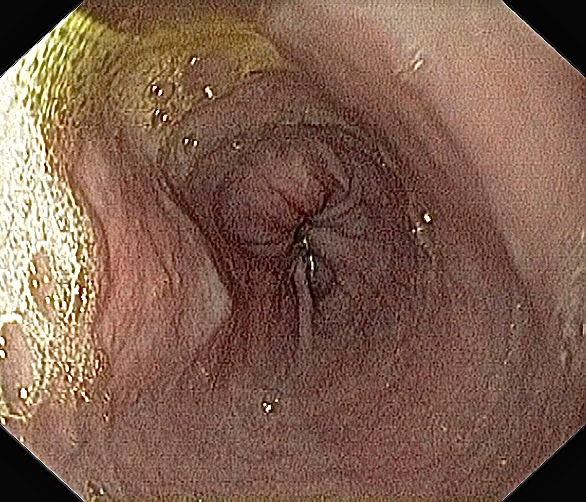

Slimhinnen i spiserøret mitt er nesten helt uten betennelse. Rosa, glatt og fint!

Omtrent samme bilde som ovenfor, tatt av meg tidligere. Bildet viser øsofagitt (betennelse i slimhinnene i spiserøret) forårsaket av hyppig oppkast, refluks av magesyre og overvekst av sopp og bakterier.